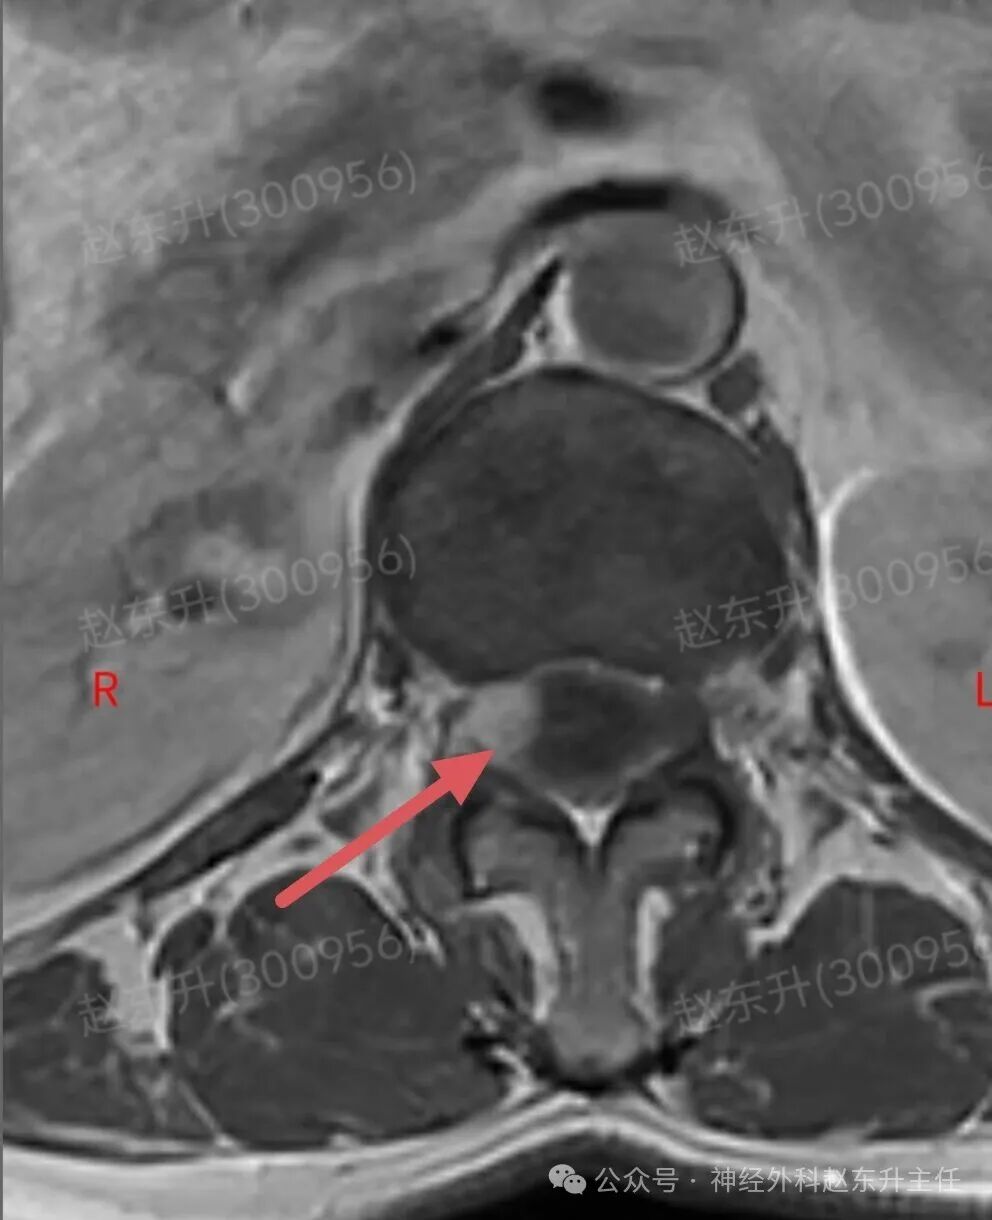

上周门诊来了一位58岁女性,患者因为下肢和腰背部顽固性疼痛半年,在各大医院就诊曾行针灸按摩,艾灸电疗等治疗没见缓解,而且疼痛评分可以达到8-9分,口服止痛药无效,康复理疗无效。随后查了一下腰椎磁共振,发现胸12腰1节段脊髓内异常信号,随后收入我科。入院之后查肌电图提示下肢和骶神经损伤严重,随后我们在全麻下使用显微镜,并且术中电生理监测下,给予脊髓内肿瘤次全切除,术后病理提示是胶质瘤。术后第2天我们就给他用了经颅磁刺激等神经康复治疗,虽然术后第1天右下肢肌力较术前减退,但经过10天的治疗以后,下肢肌力逐渐恢复,可以下地行走了。术后他还需要进一步的放疗和化疗来抑制肿瘤的生长,预防肿瘤复发。

图片图片图片图片图片图片图片图片切除的肿瘤图片术后病理西安市红会医院神经外科赵东升主任介绍:脊髓内胶质瘤是一种起源于脊髓实质内部的胶质细胞(即神经系统的“支持”细胞)的肿瘤。与脊膜瘤(位于脊髓外)的关键区别在于,它生长在脊髓内部,因此会浸润并破坏正常的脊髓神经组织核心特征:性质:涵盖从低级别良性到高级别恶性的完整谱系,但以低级别为主。位置:完全位于脊髓中央,可累及多个脊髓节段,甚至全长脊髓。特点:肿瘤与正常脊髓组织边界不清(浸润性生长),手术全切极为困难。其生长直接破坏神经传导束,导致严重神经功能障碍。发病率:相对少见,约占所有中枢神经系统胶质瘤的2-4%,但却是儿童最常见的髓内肿瘤。无明显性别差异。与脊膜瘤的关键区别总结

主要类型1.室管膜瘤(约占60%):常见的成人髓内胶质瘤。多为低级别(WHO I级和II级),生长缓慢。常发生于颈段和胸段,常有明确边界,有时可有“假包膜”,是手术全切希望最大的一种。2.星形细胞瘤(约占30%):常见的儿童髓内胶质瘤。从低级别(毛细胞型星形细胞瘤,WHO I级,预后好)到高级别(胶质母细胞瘤,WHO IV级,预后极差)都有。浸润性生长为特点,与正常脊髓几乎无边界,手术全切风险极高。3.其他少见类型:如血管母细胞瘤(常与VHL病相关)、少突胶质细胞瘤等。临床表现(症状)症状因肿瘤生长缓慢而隐匿、渐进性加重,早期易被忽视。典型症状:1.感觉障碍(最早、最常见):l分离性感觉障碍:这是特征性表现。由于肿瘤侵犯脊髓中央的白质前连合,导致痛觉、温觉纤维受损,而触觉、深感觉保留。患者表现为双侧对称性的、节段性的痛温觉减退或消失,而触觉正常l麻木、酸痛、束带感。2.运动障碍:n肿瘤平面以下出现肢体无力、僵硬、肌肉萎缩(尤以手部小肌肉萎缩常见)。n行走困难,步态不稳。3.疼痛:定位不明确的颈背部疼痛,夜间痛可能更明显。4.自主神经功能障碍(晚期):l大小便失禁或困难。l性功能障碍。l皮肤营养障碍(无汗、皮肤干燥等)。诊断增强磁共振(MRI): 是首选和确诊的关键检查。典型表现:可见脊髓呈梭形、偏心性或中心性增粗。肿瘤在T1像呈等或低信号,T2像呈高信号,增强后强化模式多样(可均匀、不均匀或环形强化)。可清晰显示肿瘤范围、有无囊变、脊髓空洞等。CT:价值有限,主要用于评估是否有脊椎骨质改变。治疗治疗远比脊膜瘤复杂,需在多学科团队(神经外科、肿瘤科、放疗科)指导下进行个体化综合治疗手术治疗(首要且核心):l目标:在最大限度保护神经功能的前提下,实现最大安全程度的肿瘤切除。全切是目标,但常因肿瘤边界不清而无法实现。l技术:在术中神经电生理监测(监测运动、感觉传导束功能)的保驾护航下,使用显微外科技术、超声吸引、激光等进行精细操作。功能保护优先于肿瘤全切放射治疗:主要适用于:高级别胶质瘤术后辅助治疗、无法全切的低级别胶质瘤术后残留、肿瘤复发无法再次手术者。化学治疗:l对于高级别(恶性)脊髓胶质瘤,可参照脑胶质瘤方案进行化疗(如替莫唑胺)。l对于部分复发的低级别胶质瘤也可能使用。预后与随访预后差异巨大,高度依赖于肿瘤的病理类型和分级l低级别室管膜瘤:若能实现全切,预后良好,可达到长期无进展生存,甚至临床治愈。复发率低。l低级别星形细胞瘤(如毛细胞型):全切后预后也很好。次全切后也可能长期稳定。l高级别胶质瘤(如胶质母细胞瘤)预后极差,即使积极治疗,也极易在脊髓内播散复发,生存期短。l随访:术后需定期(通常每3-6个月,后逐渐延长)进行增强MRI复查,监测肿瘤是否残留或复发。神经功能康复治疗至关重要赵东升主任简介医学硕士,西安市红会医院北院区神经外科主任医师,从事神经外科近20年。使用独创的“三维一体疗法”成功促醒大量昏迷病人,使上百例脊髓损伤瘫痪患者重新站起来。最早在陕西省开展第一例脊髓电刺激治疗昏迷病人,第一例脊髓电刺激手术治疗截瘫病人,第一例脊髓电刺激手术治疗下肢缺血顽固性疼痛。主编专著3部,参编专著11部,发表学术论文30余篇,荣获国家专利32项(其中四项发明专利),担任多部杂志编委及审稿专家。擅长:1.脑病方面:昏迷促醒,脑肿瘤、脑积水、脑梗死偏瘫、肌张力增高、顽固性癫痫、三叉神经痛、脑干出血、老年痴呆、帕金森、头痛等;2.脊髓病方面:脊髓损伤、脊柱术后疼痛、大小便障碍、脊髓肿瘤、脊髓空洞、小脑扁桃体下疝畸形、脊髓栓系、脊膜膨出、痉挛性截瘫等;3.周围神经疾病方面:糖尿病足、下肢缺血性疼痛、臂丛神经损伤、腓总神经损伤、腕管综合征、肘管综合征、男性功能障碍等门诊时间:北院区:周一全天门诊二楼203A  第五诊室南院区:周二全天门诊三楼310诊室